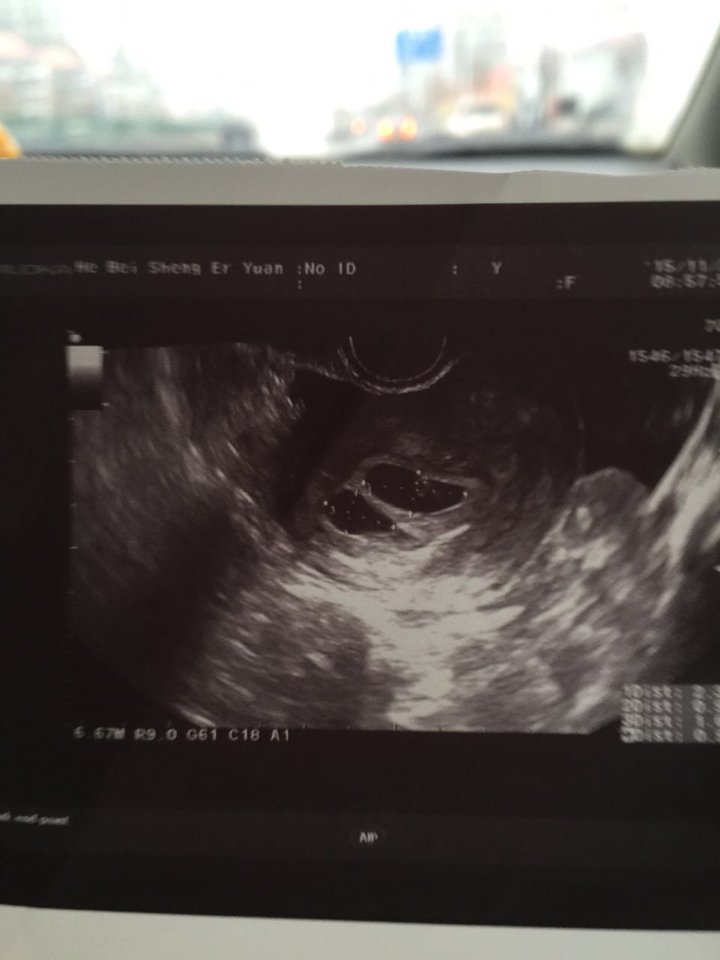

试管婴儿移植一个月一超两个孕囊,一个见胎芽心血管搏动,一个未见,大的23 10小的16 9是不是小

试管婴儿移植一个月一超两个孕囊,一个见胎芽心血管搏动,一个未见,大的23 10小的16 9是不是小的很渺茫已经停止发育了?

通常情况北则下超过25mm还是看不到胚芽考虑是空囊妊娠。所以建议一周后再检查,都堡怪会出现的,只是时间唤绣趋问题。祝平安健康!